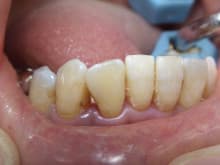

下の前歯にダイレクト治療を行った症例についてご紹介します。

プラスチックが詰めてあり

その中が2次虫歯になっていたました。

治療前です。